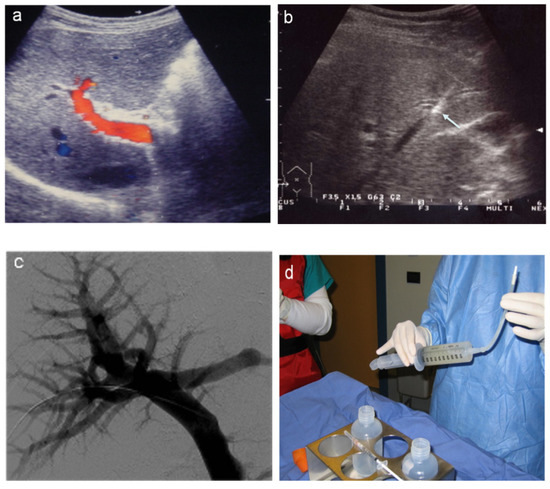

5. Intra-Portal Islet Auto-Transplantation